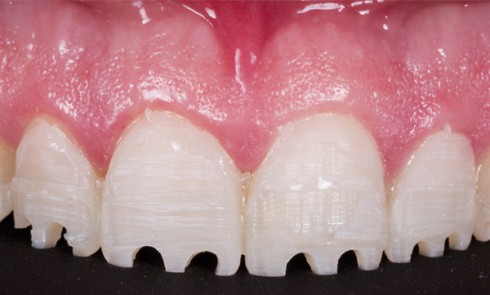

Article réservé à nos abonnés Restaurations esthétiques en céramique collée (RECC) et traitement de l’usure : chronologie clinique

La prise en charge thérapeutique d’une denture usée par érosion, attrition, abrasion ou, plus souvent, par une association de ces...